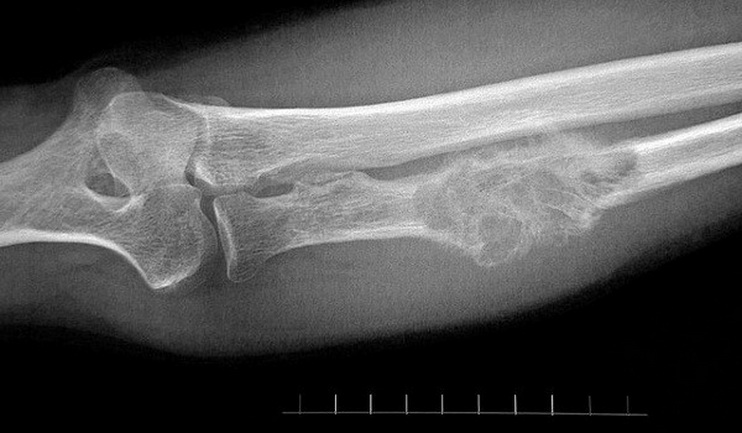

Для постановки диагноза врач должен назначить рентгенографию костей. Однако самым точным способом диагностики будет являться биопсия подозрительного участка кости. Для выявления имеющихся метастазов назначают КТ.